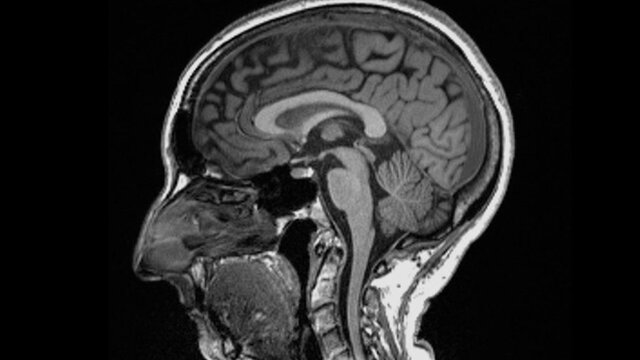

به گزارش سایت طلا ، متخصصان در بررسی های خود تفاوت های قابل توجهی در اسکن MRI افراد، قبل و بعد از ابتلا به بیماری کووید-۱۹ پیدا کردند.

به گفته آنان حتی پس از ابتلا به نوع خفیف بیماری، اندازه کلی مغز اندکی کوچک شده و ماده خاکستری کمتری در بخشهای مربوط به بویایی و حافظه وجود داشته است.

- اندازه کلی مغز افراد آلوده به کروناویروس بین ۰.۲ تا ۲ درصد کوچک شده بود.

- از میزان ماده خاکستری در نواحی بویایی مرتبط با بویایی و مناطق مرتبط با حافظه کاسته شده بود.

- افرادی که به تازگی از کووید بهبود یافته بودند، در انجام امور ذهنی پیچیده، کمی مشکل داشتند.